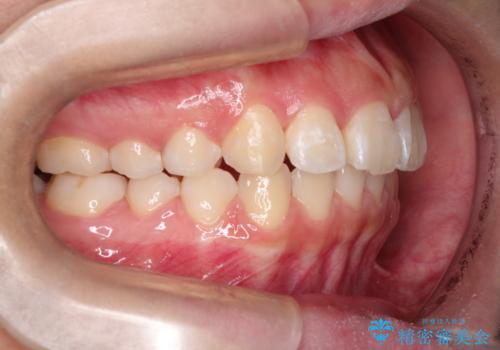

- 前歯が出ているのを主訴に来院されました。

上の前歯が前方に傾斜しており、上の前歯と下の前歯が接触していない状態でした。

上の奥歯を後方に移動させて、前歯を引っ込める計画としました。